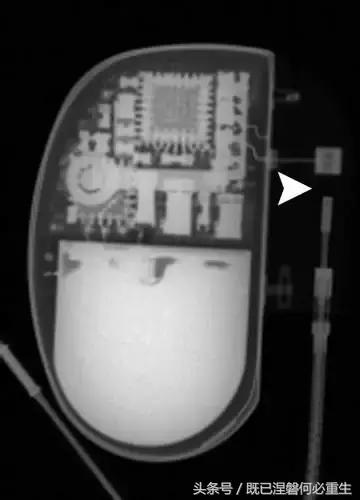

图。 9发生器引线断开。 移出的装置的放射线照片显示从末端完全退出的电极的外观(箭头)。 少数发电机没有容易识别的标志; 因此,制造商不能确定。